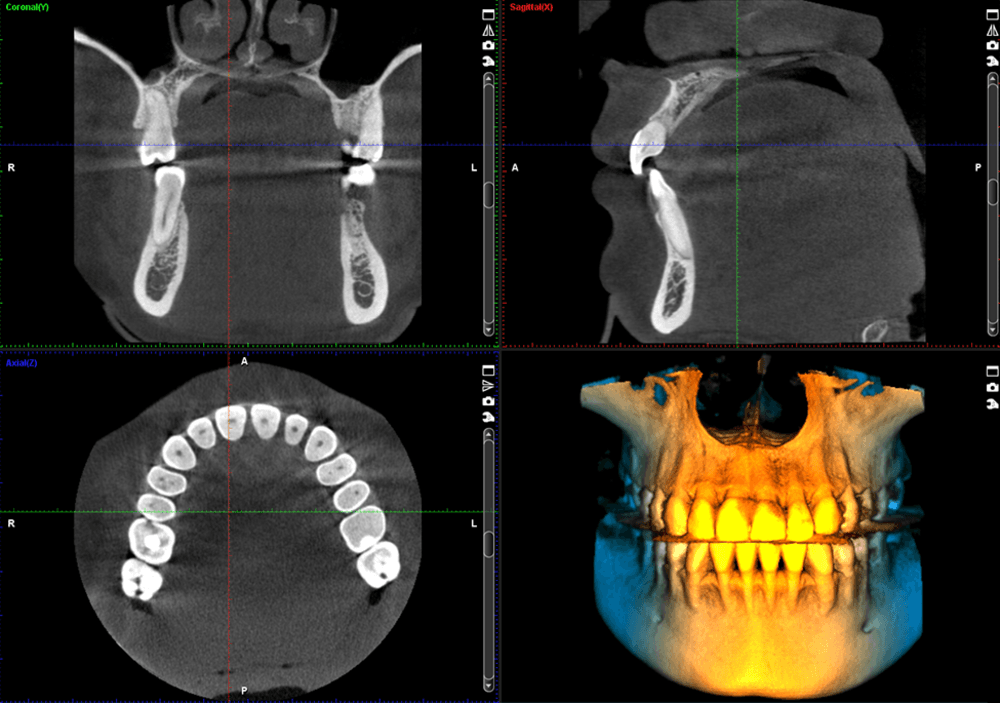

Meet the Planmeca ProMax® 3D imaging family, a comprehensive suite of solutions tailored to meet the unique demands of dental practices. With unparalleled image quality and cutting-edge technology, these systems provide practitioners with the versatility and precision needed for accurate diagnostics and treatment planning.

Discover the Planmeca ProMax® 3D family, meticulously designed to meet the needs of every dental practice. Known for its unparalleled image quality, each system reflects Planmeca's commitment to excellence. Equipped with noise reduction technology, these units deliver unmatched image clarity. Enjoy True Extraoral bitewings, segmented pans, and AutoFocus for crystal clear pan images every time. Available features like Planmeca Ultra Low Dose™ and Planmeca CALM® for patient safety